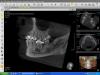

doktorenok Опубликовано 29 октября, 2011 Поделиться Опубликовано 29 октября, 2011 Тоже киста, тоже в 4 сегменте. Пятый на сегодняшний день живой, холодное чувствует. Вопрос: депульпировать его до удаления шестого или после удаления шестого, если потеряем витальность? Или без разницы? Или вообще не трогать? Кто как поступает в таких ситуациях? Ссылка на комментарий

DocNikNik Опубликовано 31 октября, 2011 Поделиться Опубликовано 31 октября, 2011 Все зависит от близости расположения кисты к корню интактного зуба. Если по R-гр. сосудисто-нервный пучек вовлечен в оболочку кисты или сдавливается ею (а в данном случае он значительно оттиснен), то проводится предварительная подготовка к операции - эндодонтическое лечение. Далее в данном случае проводим экстракцию 46, цистэктомию с резекцией верхушки корня 45. Лоскут выкроить между 44 и 45 вниз, ушить область медиального корня 46, в дистальном - кюретаж и под иодоформную турунду. Удичи! Ссылка на комментарий

FBR Опубликовано 11 ноября, 2011 Поделиться Опубликовано 11 ноября, 2011 (изменено) А зачем резекция верхушки 45 зуба?Такой же вопрос к коллеге, а еще не плохо было бы фамилию пациентки замазать чем нибудь(закон о защите персональных данных и все такое). Еще немного смущает костный рисунок в области 38 апикально. Я бы еще рентгенологу показал снимок. Изменено 11 ноября, 2011 пользователем FBR Ссылка на комментарий